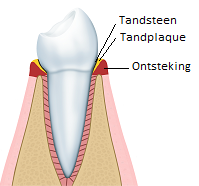

Stadium 1: Gingivitis

Gingivitis is het eerste stadium van een lichte tandvleesontsteking en is te herkennen aan rood, slap en gezwollen tandvlees en/of bloedend tandvlees bij het eten en/of poetsen.

Daarnaast kunnen een vieze smaak of een slechte adem duiden op gingivitis. Gingivitis veroorzaakt zelden pijnklachten. Om ontstoken tandvlees te genezen, is goed tandenpoetsen en tussen de tanden en kiezen reinigen van belang.